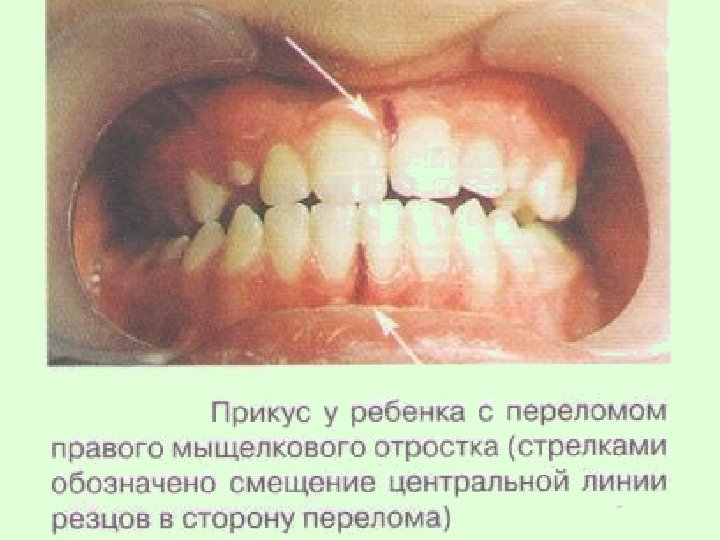

Для односторонних переломов суставного отростка, чаще возникающих при падении на подбородок, характерным является: 1) ограниченное открывание рта и наличие болезненного отека тканей околоушной области; 2) асимметрия лица за счет смещения челюсти в сторону перелома; 3) боль на стороне перелома при надавливании на подбородок; 4) смещение средней линии в больную сторону.

При двустороннем переломе суставных отростков у детей до 7 лет смещения отломков практически не происходит, а чаще возникают переломо-вывихи головки или переломы шейки суставного отростка по типу "зеленой ветки". Тогда ребенка тревожит боль в височнонижнечелюстном суставе при жевании и нажатии на подбородок. У детей старшего возраста преобладают переломы суставных отростков со смещением, тогда обе ветви нижней челюсти смещаются кверху, а нижняя челюсть — назад, поэтому возникает открытый и дистальный прикус.